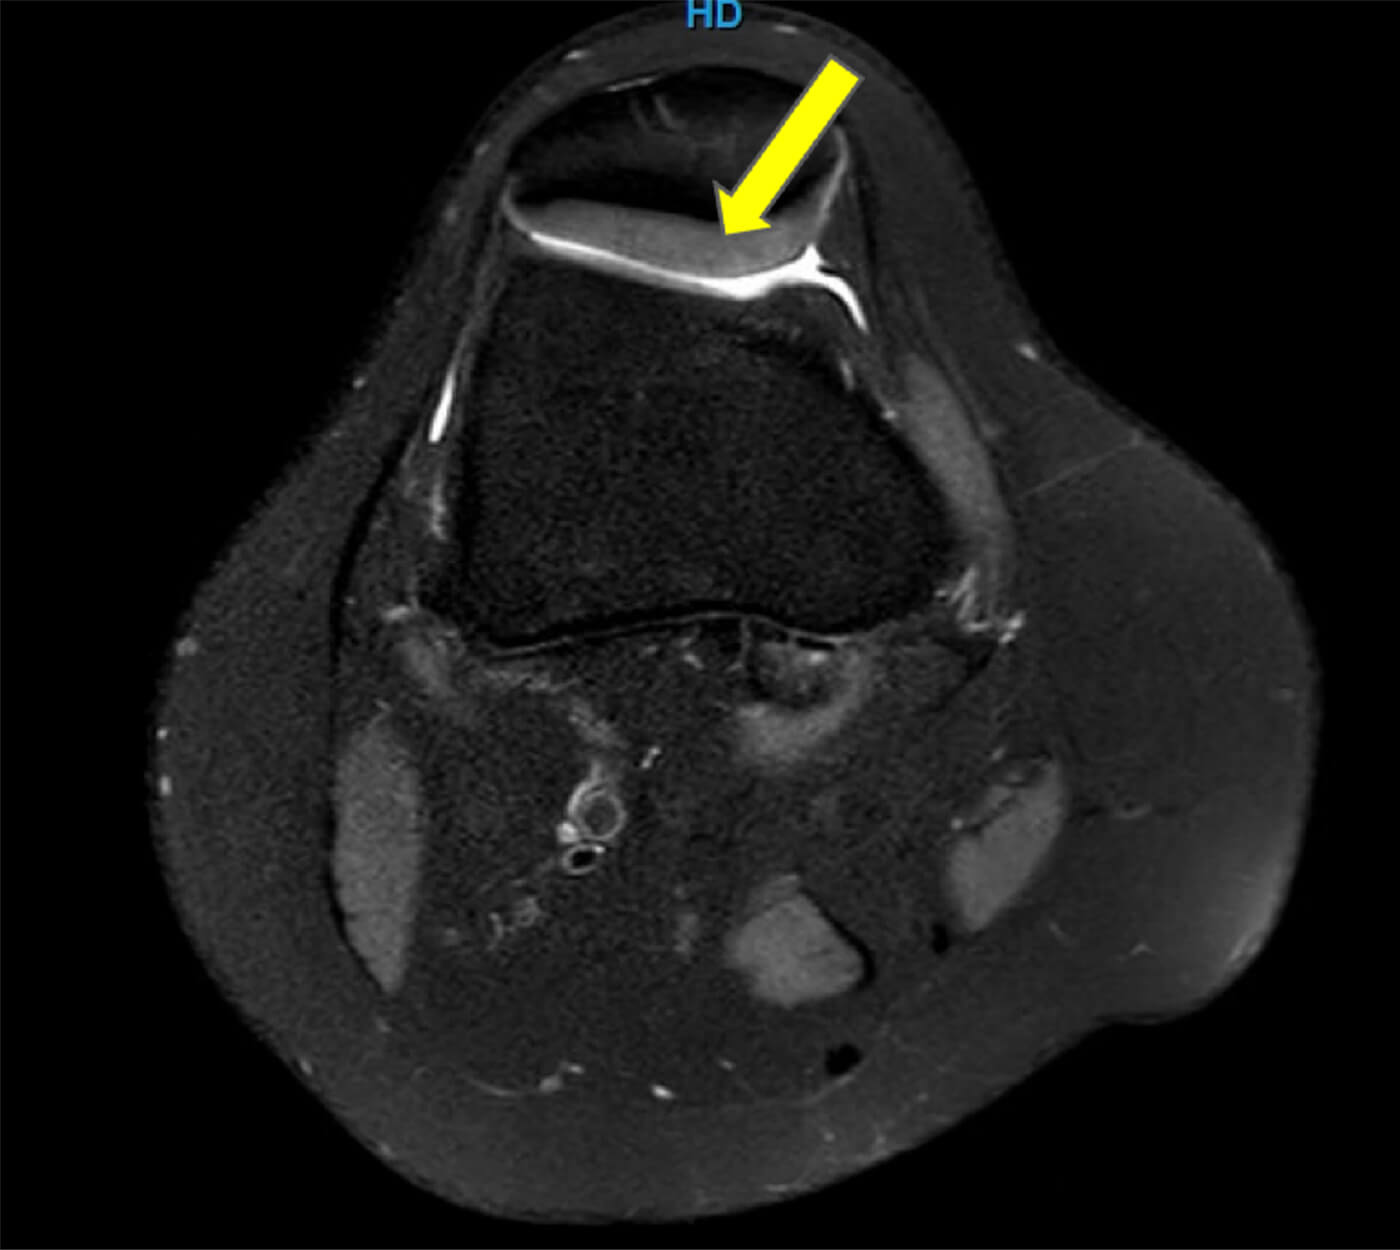

Het kan zijn dat de diagnose niet zo duidelijk is als je hoopt dat die is. Dan wordt geregeld een MRI-scan ingezet om het kraakbeen van de knieschijf, het binnenste van de knie, de bandjes rondom de knie en andere structuren te beoordelen. Het komt vaak voor dat een MRI van de knie bij iemand met PFPS niet afwijkend is. Dat is alleen maar prettig en betekent niet dat er niets aan de hand is. Wel betekent dit dat er geen structurele beschadiging aan de knie te zien is. Wel kan het nog steeds zo zijn dat er te veel druk achter de knieschijf bestaat en er een functieprobleem is opgetreden.

Een MRI-scan met bovenaanzicht van de knie (axiale opname) waarbij het kraakbeen achter de knieschijf (gele pijl) en de positie hiervan goed te beoordelen is.